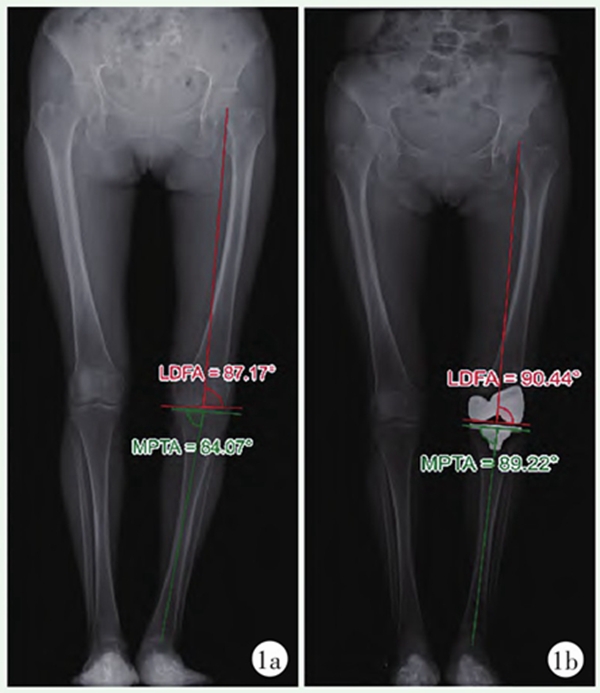

图2 KA-TKA患者双下肢站立位全长X线片

2a:术前X线片;2b:术后X线片患者术前股骨及胫骨排列予以完全保留;LDFA:股骨远端外侧角;MPTA:胫骨近端内侧角

KA由Howell等于2006年提出,该理念要求将假体与膝关节三条运动轴匹配,即髌骨矢状面旋转轴,胫骨矢状面旋转轴,胫骨水平面旋转轴,三条运动轴与患者关节炎前的关节线要么平行,要么垂直,因此,通过平行关节面进行截骨便可实现该目标。对于截骨量,Howell提出可通过游标卡尺对其进行精确测量,可将误差控制在0.5mm的范围内,最终达到在安装假体后可完全还原患者膝关节炎前解剖形态的目的(截骨量=假体厚度-锯片厚度-磨损软骨厚度)。KA是真正的膝关节表面置换技术,旨在通过重建患者特有的生理结构而创造一个解剖友好型膝关节,降低对软组织松解的需求(图2)。